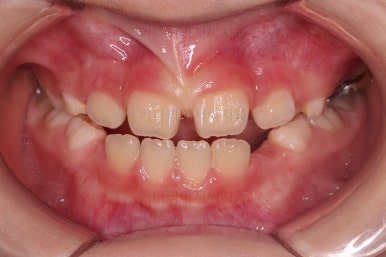

초진 시 입안의 모습입니다.

아래쪽 치열이 전반적으로 윗니보다 앞쪽에 위치한 전형적인 앵글씨 3급 부정교합인데요.

어금니에서부터 앞니까지 아랫니가 윗니보다 앞쪽에 위치하네요.

특히 앞니는 아랫니가 윗니보다 나와있는 "반대교합" 상태였고요.

또한 위아래로 겹침이 없고 떠있는 "개방교합" 상태였어요.

즉, 앵글씨 3급 부정교합 - 반대교합 - 개방교합 등 굉장히 복합적인 교합의 문제를 가진 환자였습니다.